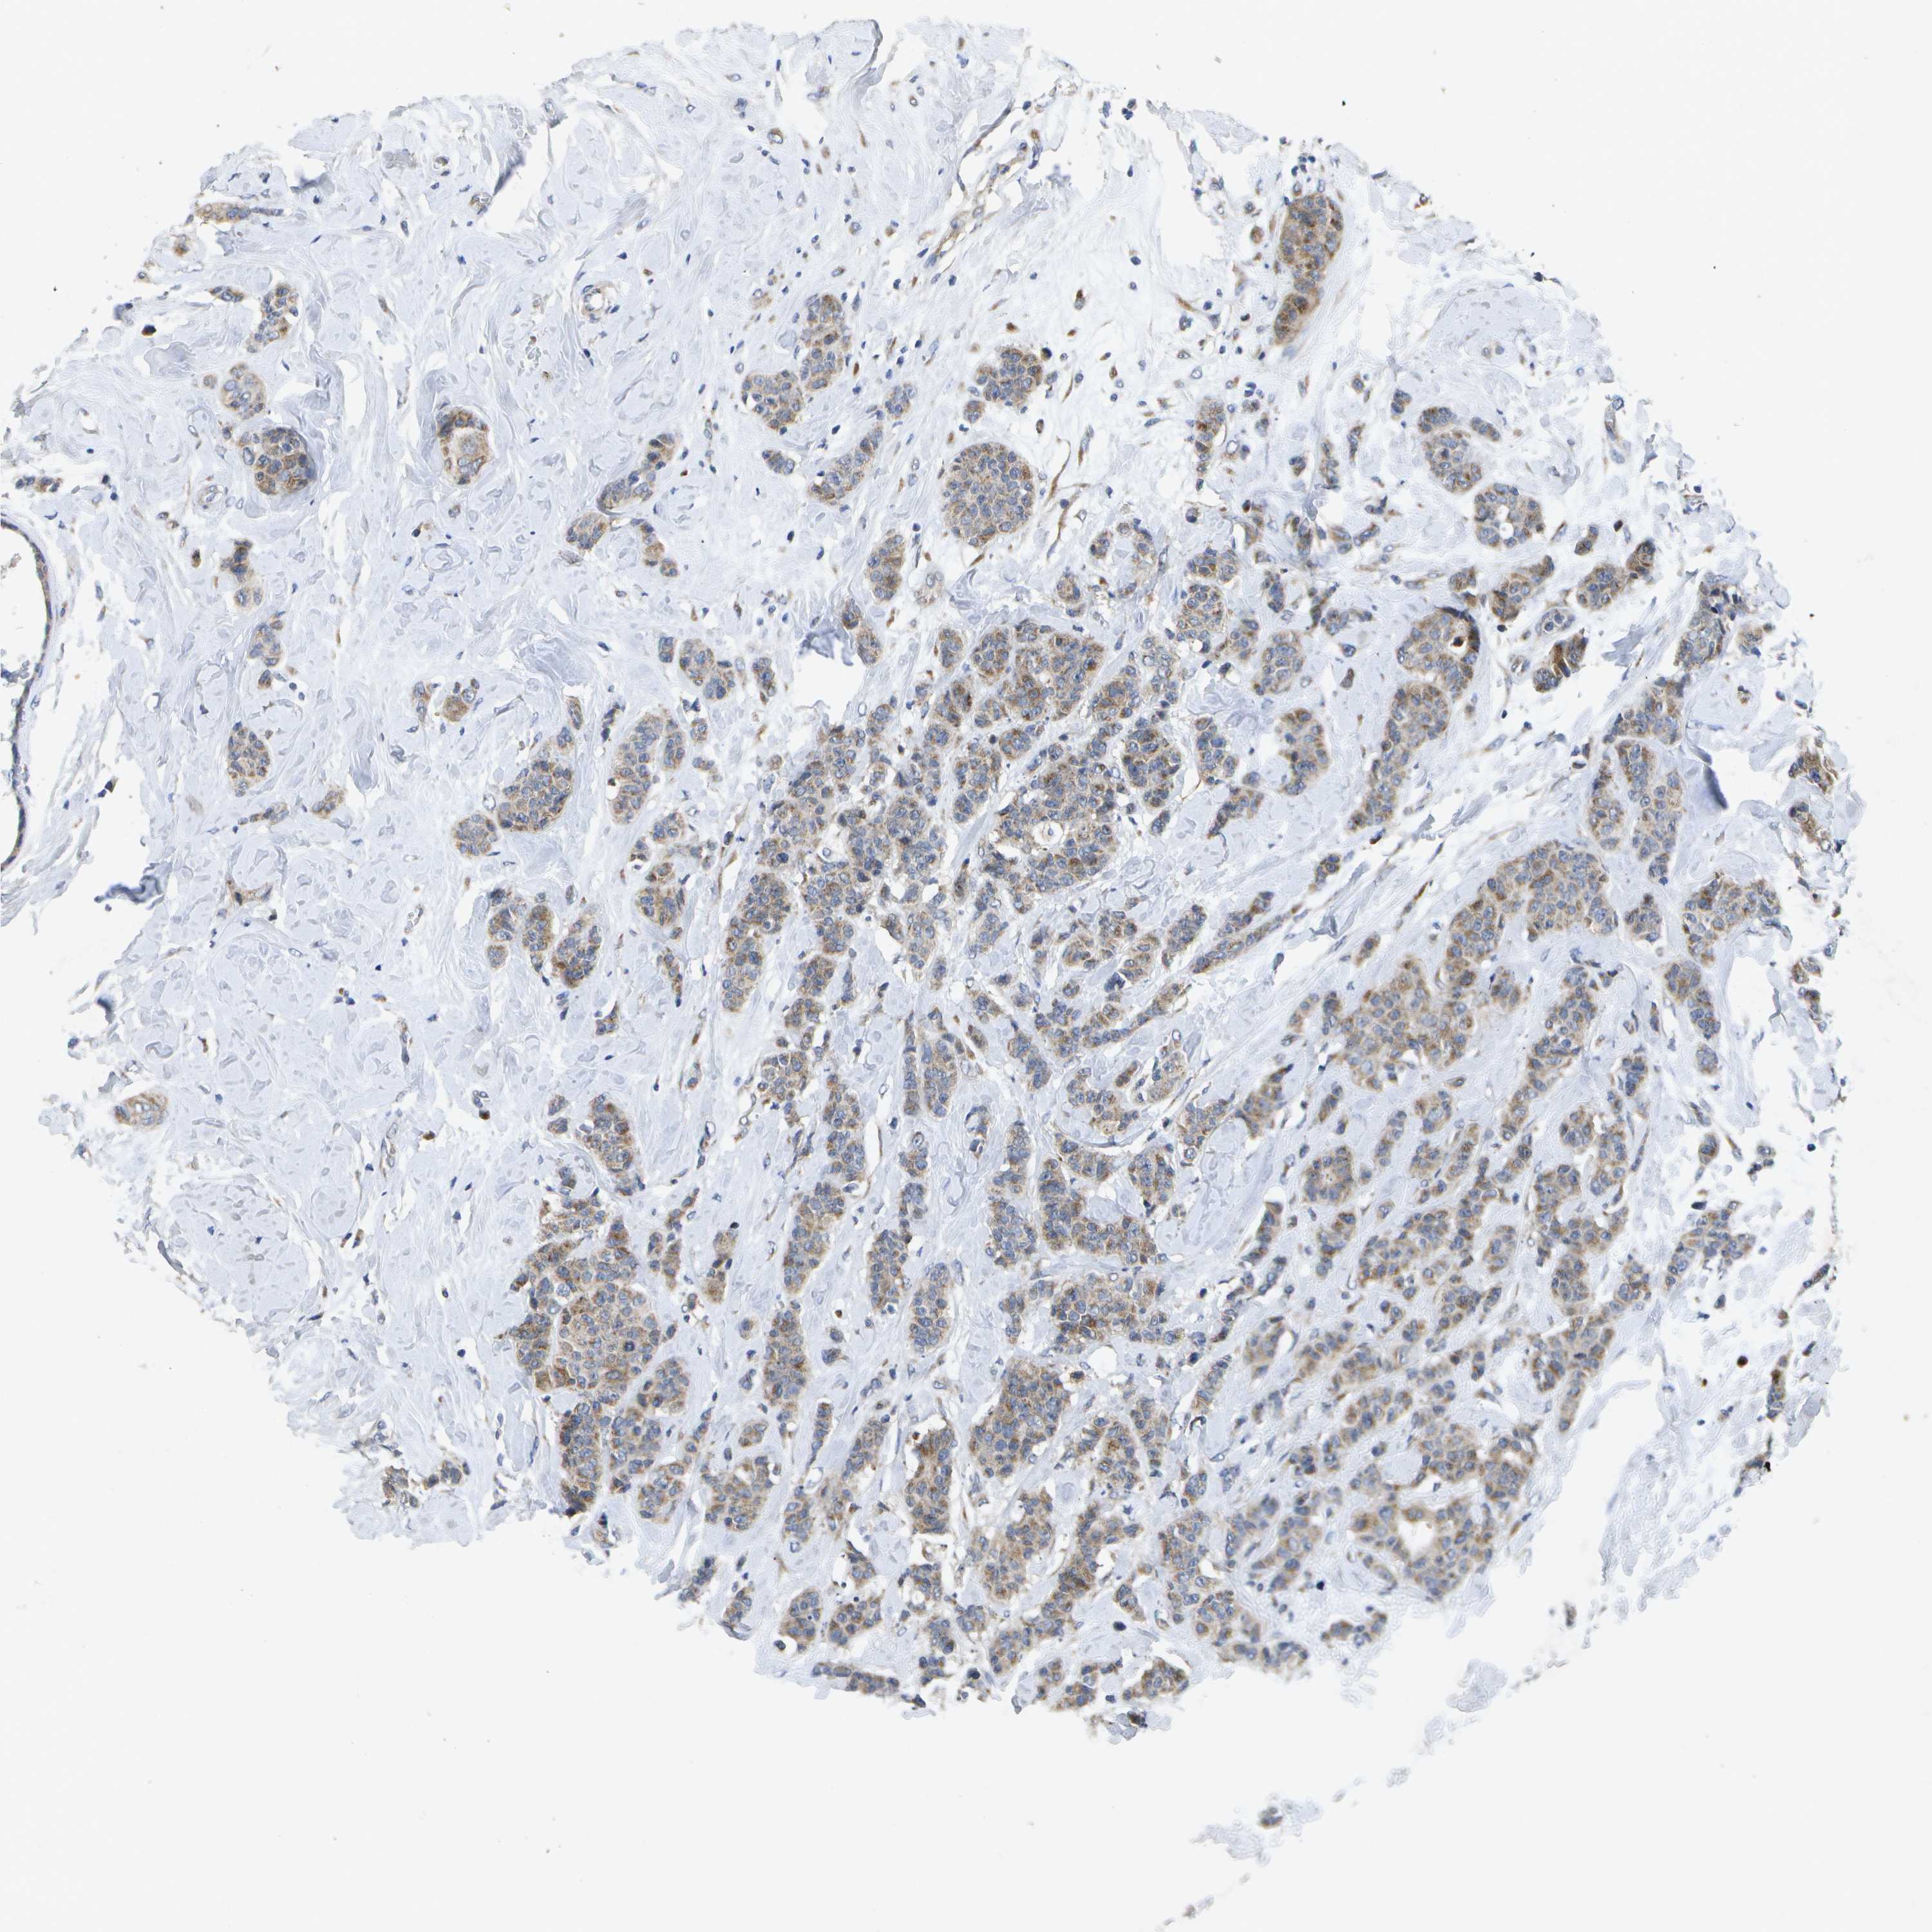

BRCA TCGA BRCA VALIDATION PROTEIN EXPRESSION